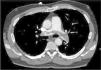

Blood test revealed a D-dimer level of 33,410 (normal<500). The electrocardiogram showed sinus rhythm at 80bpm, with a S1Q3T3 pattern. Arterial blood gas analysis revealed respiratory alkalosis and partial respiratory failure. PE was suspected, so a chest angio-CT scan was conducted (Fig. 1), in which direct evidence was observed of a massive PE that manifested as a partially recanalized thrombus straddling the two main branches, and bilateral thrombosis in segmental arteries, along with signs of right ventricular overload.

Given the suspected diagnosis of paradoxical embolism through a PFO, a transthoracic echocardiography and a subsequent transesophageal echocardiography were requested (Fig. 2). This revealed an aneurysm of the atrial septum with PFO, mild left ventricular hypertrophy and mild mitral regurgitation. Tricuspid regurgitation was not observed in any of the ultrasound examinations, so systolic pulmonary pressure could not be calculated. However, mild pulmonary insufficiency, with a mean pulmonary acceleration time of 140ms and normal mean pulmonary artery pressure of 20mmHg was detected. The diagnosis of left popliteal DVT and massive PE secondary to long traveling hours was established, with paradoxical embolism in the right arm due to PFO.

Image 1 (apical view of the four chambers obtained by transthoracic ultrasound): baseline image after injection of contrast material (agitated saline). Higher echogenicity is seen in the right ventricle and right atrium (more grayish color due to microbubbles) and, without the need of Valsalva maneuver, passive passage of microbubbles to the left heart occurs (small hyperechoic spheres). Image 2 (cross-sectional bicaval plane on transesophageal ultrasound): fossa ovalis membrane detachment of up to 3mm.